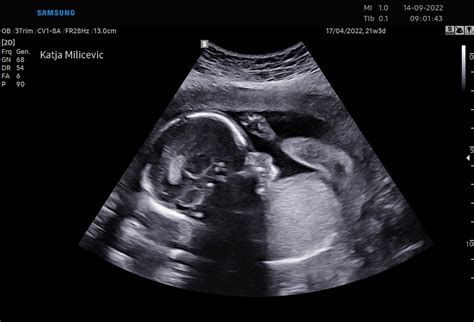

Ultrazvočni pregled: Zakonodaja omogoča pri normalni enoplodni nosečnosti dva ultrazvoka. Prvega v zgodnji nosečnosti, drugi pregled z ultrazvokom je pregled morfologije ploda med 20. in 22. tednom. Če se ginekolog odloči za ultrazvok v 16. tednu, se bo najprej pogovoril z vami. Pri tem morate vedeti tudi, da zdravstvena zavarovalnica pokrije le stroške za določeno število ultrazvočnih pregledov.